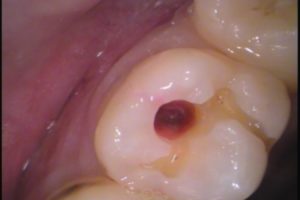

表面から歯を削っていきます。

出てきましたね!

噛む面からの虫歯は、溝の隙間から進入し、

歯の中で広がるので、目で見ただけでは虫歯の深さは分かりにくいです。

う蝕検知液(虫歯染色液)を用いて、虫歯菌がいる部分だけを丁寧に取り除いていきます。

う蝕検知液は、虫歯の部分を特異的に染めるので、確認しながら虫歯を除去します。

綺麗に取り除きました。

想像以上に大きいです!